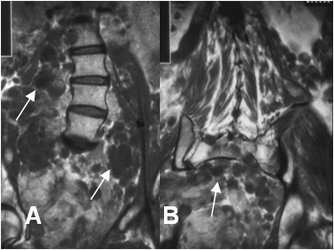

Fig 180. Neurofibroma.

A: RM sagital en T1. Lesión fusiforme central e isointensa al músculo, que presenta continuidad con el nervio ulnar.

B: RM sagital en T2 y C: RM coronal en STIR. Imagen heterogénea, con componente quístico central e hiperintenso en ambas secuencias.